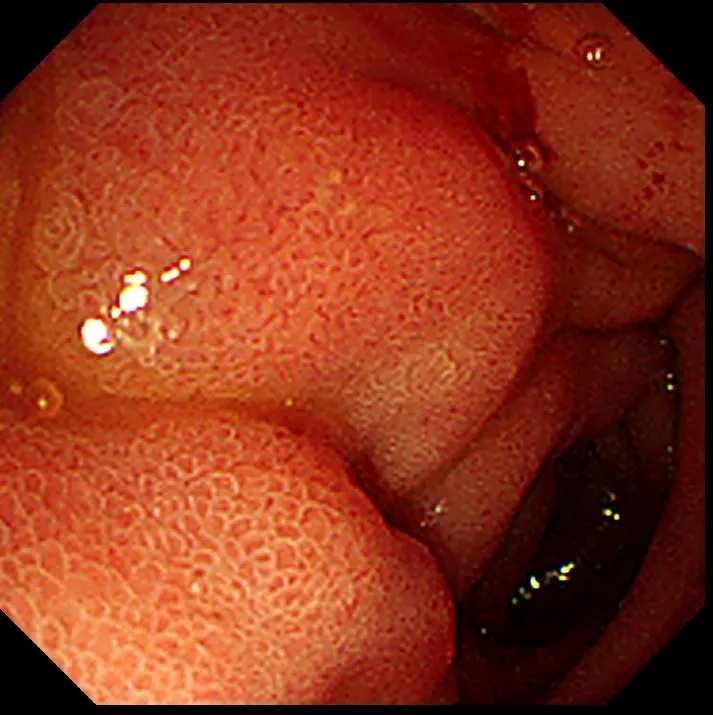

통증을 심하게 호소하였으나 시술을 하지 않으면 환자가 위험할 수 있기에 조심하면서 부어 있는 십이지장을 통과하여 십이지장 2부의 유두부에 접근할 수 있었다.(십이지장은 1부~4부까지 나뉘며, 2부에 담즙이 배출되는 곳인 유두부가 있다.) 유두부에서 탁한 색깔의 담즙을 확인할 수 있었다.

담도에서 십이지장으로 담즙이 빠져나가는 십이지장 유두부의 모습